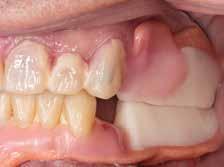

Wachsaufstellung (Abb. 8–10) erhielt das zahntechnische Labor die Freigabe zur Erstellung der Primärund Sekundärteleskope mit Gerüsten. Diese wurden insbesondere auf ihre Passgenauigkeit und Schaukelfreiheit im Kiefer überprüft. Des Weiteren wurde bei der Erstellung auf eine Unterspülbarkeit des transplantierten Gebietes geachtet. Nach erfolgter Wachsaufstellung auf Gerüst wurde die Fertigstellung der Teleskopprothesen und der Einzelzahnzirkonkrone in

Auftrag gegeben. Für Zahn 11 wurde vom zahntechnischen Labor ein entsprechendes Mock-up mit Schiene zur Übertragung erstellt (Abb. 11–23). Anschließend an die komplikationslose Eingliederung der Arbeit erfolgte eine Kontrolle sieben Tage nach erfolgter Übergabe (Abb. 24, Seite 7). Nach der Durchführung von minimalen Korrekturen an der Okklusion wurde der Patient in den Recall entlassen.•

Modellgussprothesen für den Oberkiefer und den Unterkiefer hatte, wurden diese herangezogen und als Immediatersatz erweitert sowie unterfüttert. Während der Planung entschied sich das behandelnde Ärzt:innen-Team sowohl im Ober- als auch Unterkiefer für eine teleskopierende Metallgerüstprothese. Zahn 11 wurde mittels Adhäsivtechnik aufgebaut und darüber hinaus für Zahn 21 eine Einzelzahnzirkonkrone geplant. Um eine adäquate Retention der Kronen gewährleisten zu können, wurden an fünf Zähnen gegossene Stiftaufbauten eingegliedert (Abb. 6 u. 7).